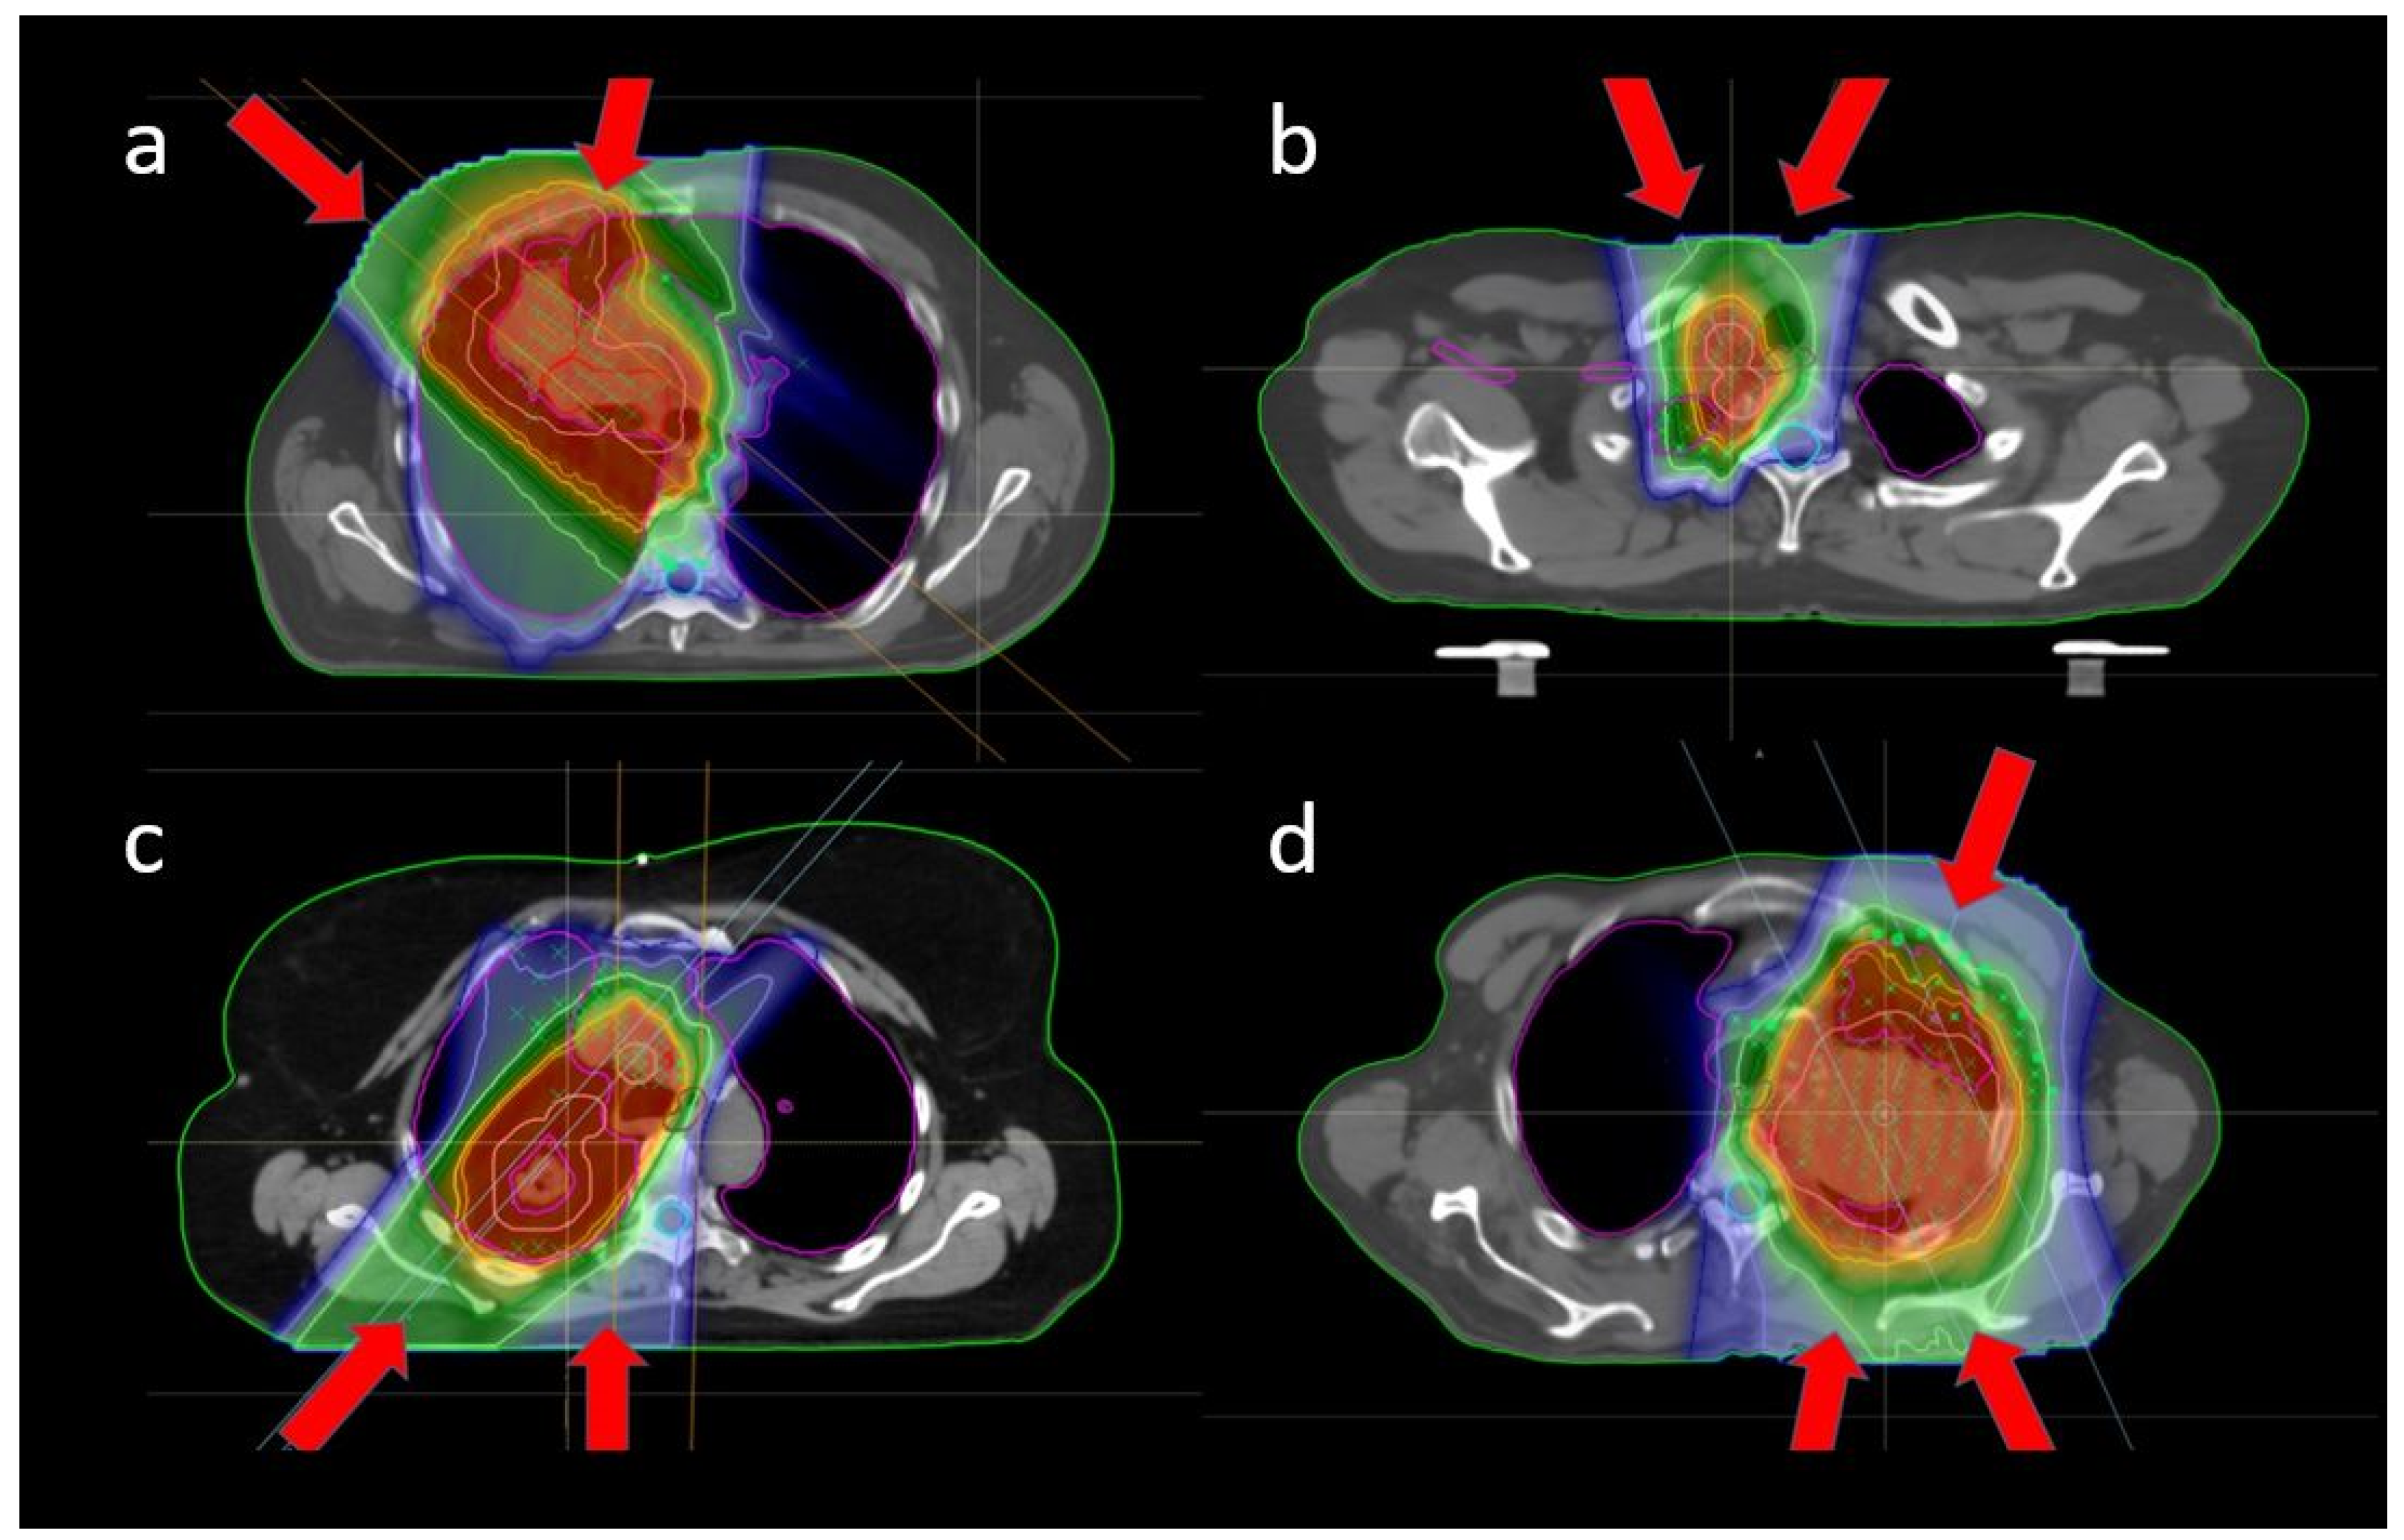

2.2. Proton Therapy Planning

2.3. Robustness Evaluation